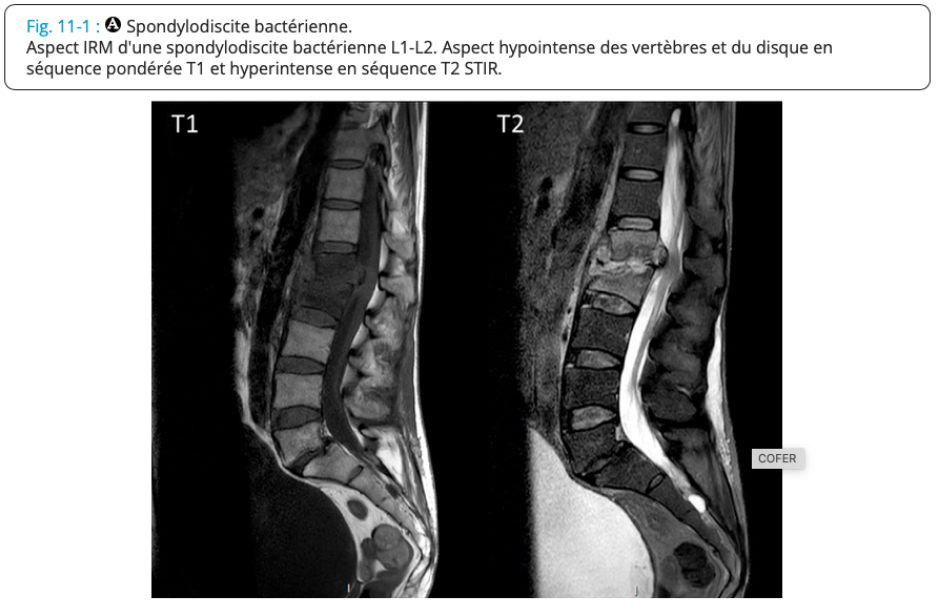

SPONDYLODISCITE INFECTIEUSE

= infection d’un disque intervertébral et des corps vertébraux adjacents

Radio : normale (début) puis décalage radio-clinique 3-4sem

IRM (exam réf diag précoce) : hypersignal du disque et des plateaux vertébraux adjacents, abcès périvertébraux ou épidurite → séquences STIR ou T1 après inj gado / hyposignal en T1

Scanner = si IRM CI, guidage ponction-biopsie discovertébrale

Scintigraphie et TEP-scanner : si IRM CI